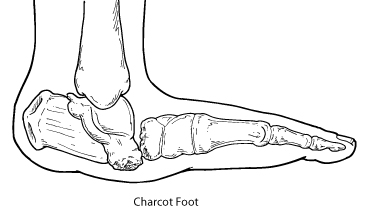

Motor nerves control muscles and give them their strength and tone. Peripheral neuropathy may also cause muscle weakness and loss of reflexes, especially at the ankle, leading to changes in the way a person walks. Foot deformities, such as bunions and hammertoes, may occur, as well as collapse of the midfoot, a condition known as Charcot foot.

In Charcot foot, the joints in the foot collapse and the foot eventually becomes deformed

The loss of foot structure may also cause shoes to rub against toes, causing sores. Blisters and sores may appear on numb areas of the foot because an injury goes unnoticed. If an infection occurs and is not treated promptly, the infection may spread to the bone, a condition known as osteomyelitis, and the foot may have to be amputated. Many amputations are preventable if minor problems are caught and treated in time.